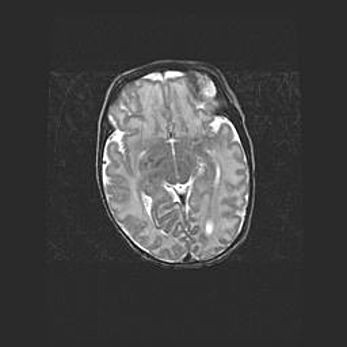

Множественные кисты обоих полушарий головного мозга, наибольшая из них в правой затылочной области. Ассиметричная атрофическая гидроцефалия.

Возраст: 7 месяцев

Вес: 5660 г

Пол: мужской

Окружность головы: 41,5 см

Срок гестации: 28-29 недель

Кисты головного мозга развиваются в результате многоочаговых некрозов вещества мозга и возникают вследствие перенесенной перинатальной инфекции, менингитов, энцефалитов, асфиксии, родовой травмы, расстройств мозгового кровообращения различного генеза. Образованию кист в веществе головного мозга плодов и новорожденных способствуют такие факторы, как высокое содержание в нем воды, недостаточная (или отсутствие) миелинизация и слабая астроглиальная реакция на повреждение.

Кисты могут сочетаться с гидроцефалией и другими поражениями головного мозга.